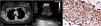

A 30-year-old female patient referred to our clinic because of the opacity located on the right lower paratracheal region, diagnosed on postero-anterior chest X-ray. She presented with complaints of chronic dry cough and weight loss. Thorax computed tomography revealed a lymphadenopathy with 20mm×15mm in length on the right lower paratracheal region (Fig. 1A). 18F-FDG (flourodeoxyglucose) PET-CT (Positron Emission Tomography-Computed Tomography) imaging revealed intense FDG-uptake value (SUVmax) with 8.7 on the lesion located at the region of 4R lymph node station (lower paratracheal region). We performed endobronchial ultrasound (EBUS) and transbronchial needle aspiration (TBNA). We visualized a well-circumscribed, round shaped, hypoechogenic lesion with the diameter of 11.6mm that was compressing the vena cava superior (Fig. 1B). Immunohistochemistry examination revealed the mesenchymal tumour cells to be strongly positive for vimentin and CD34 (Fig. 1C). Ki67 proliferation index was determined as 5%. No lymphoid cells were observed on microscopic examination. Patient was diagnosed with epithelioid hemangioendothelioma of the superior vena cava. Surgery was recommended to the patient, but she did not accept the operation.

Computed tomography showed a right lower paratracheal lesion (A), endobronchial ultrasound revealed a well-circumscribed, round shaped, hypoechogenic lesion with the diameter of 11.6mm compressing the vena cava superior (B), and immunohistochemical examination showed diffuse expression of CD34 (C).